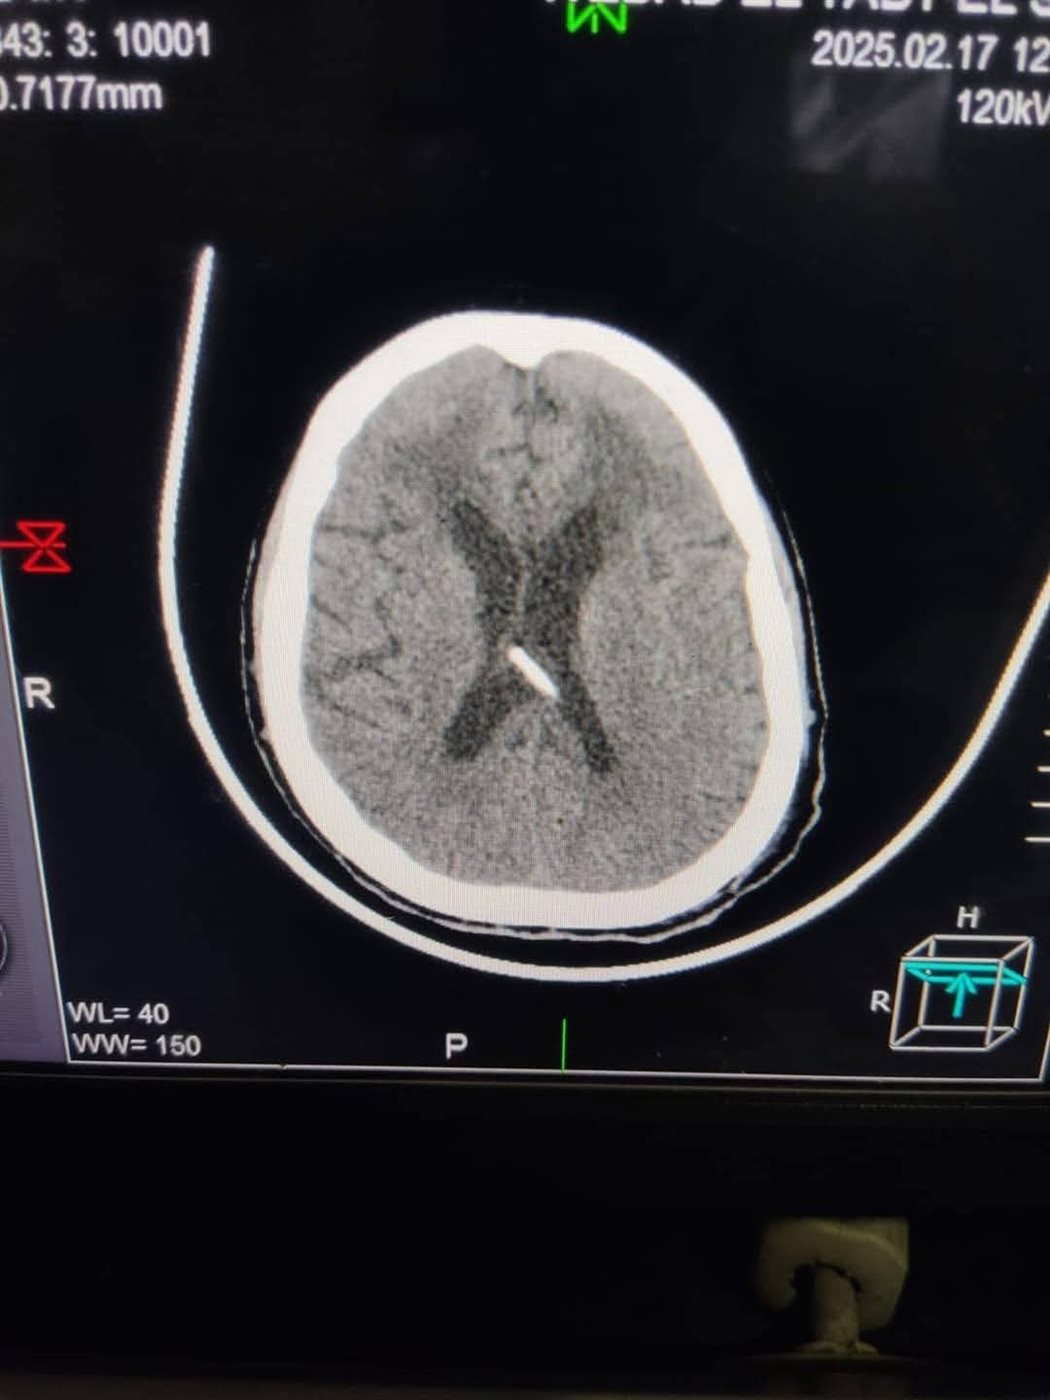

أجرى الفريق الطبى بمستشفى دمياط العام بقيادة الدكتور معاذ ياسر العبد جراحة دقيقة لتركيب صمام مخى بريتونى لمريضة تعانى من فشل كلوي وغيبوبة.

حيث تم إجراء الفحوصات اللازمة لها قبل إجراء الجراحة والتى تبين خلالها من وجود استسقاء حاد بالمخ أثر على درجة الوعى والحركة، وعليه تم التعاون مع كافة الأقسام للتجهيز لإجراء الجراحة وتركيب الصمام لصرف ضغط السائل النخاعى الزائد وخروج الحالة بدرجة وعى كاملة بعد نجاح العملية، والتى تُعد الأولى من نوعها بمستشفيات مديرية الصحة بدمياط، فى إطار الجهود المبذولة للقضاء على قوائم الانتظار بتخصص جراحات المخ والأعصاب